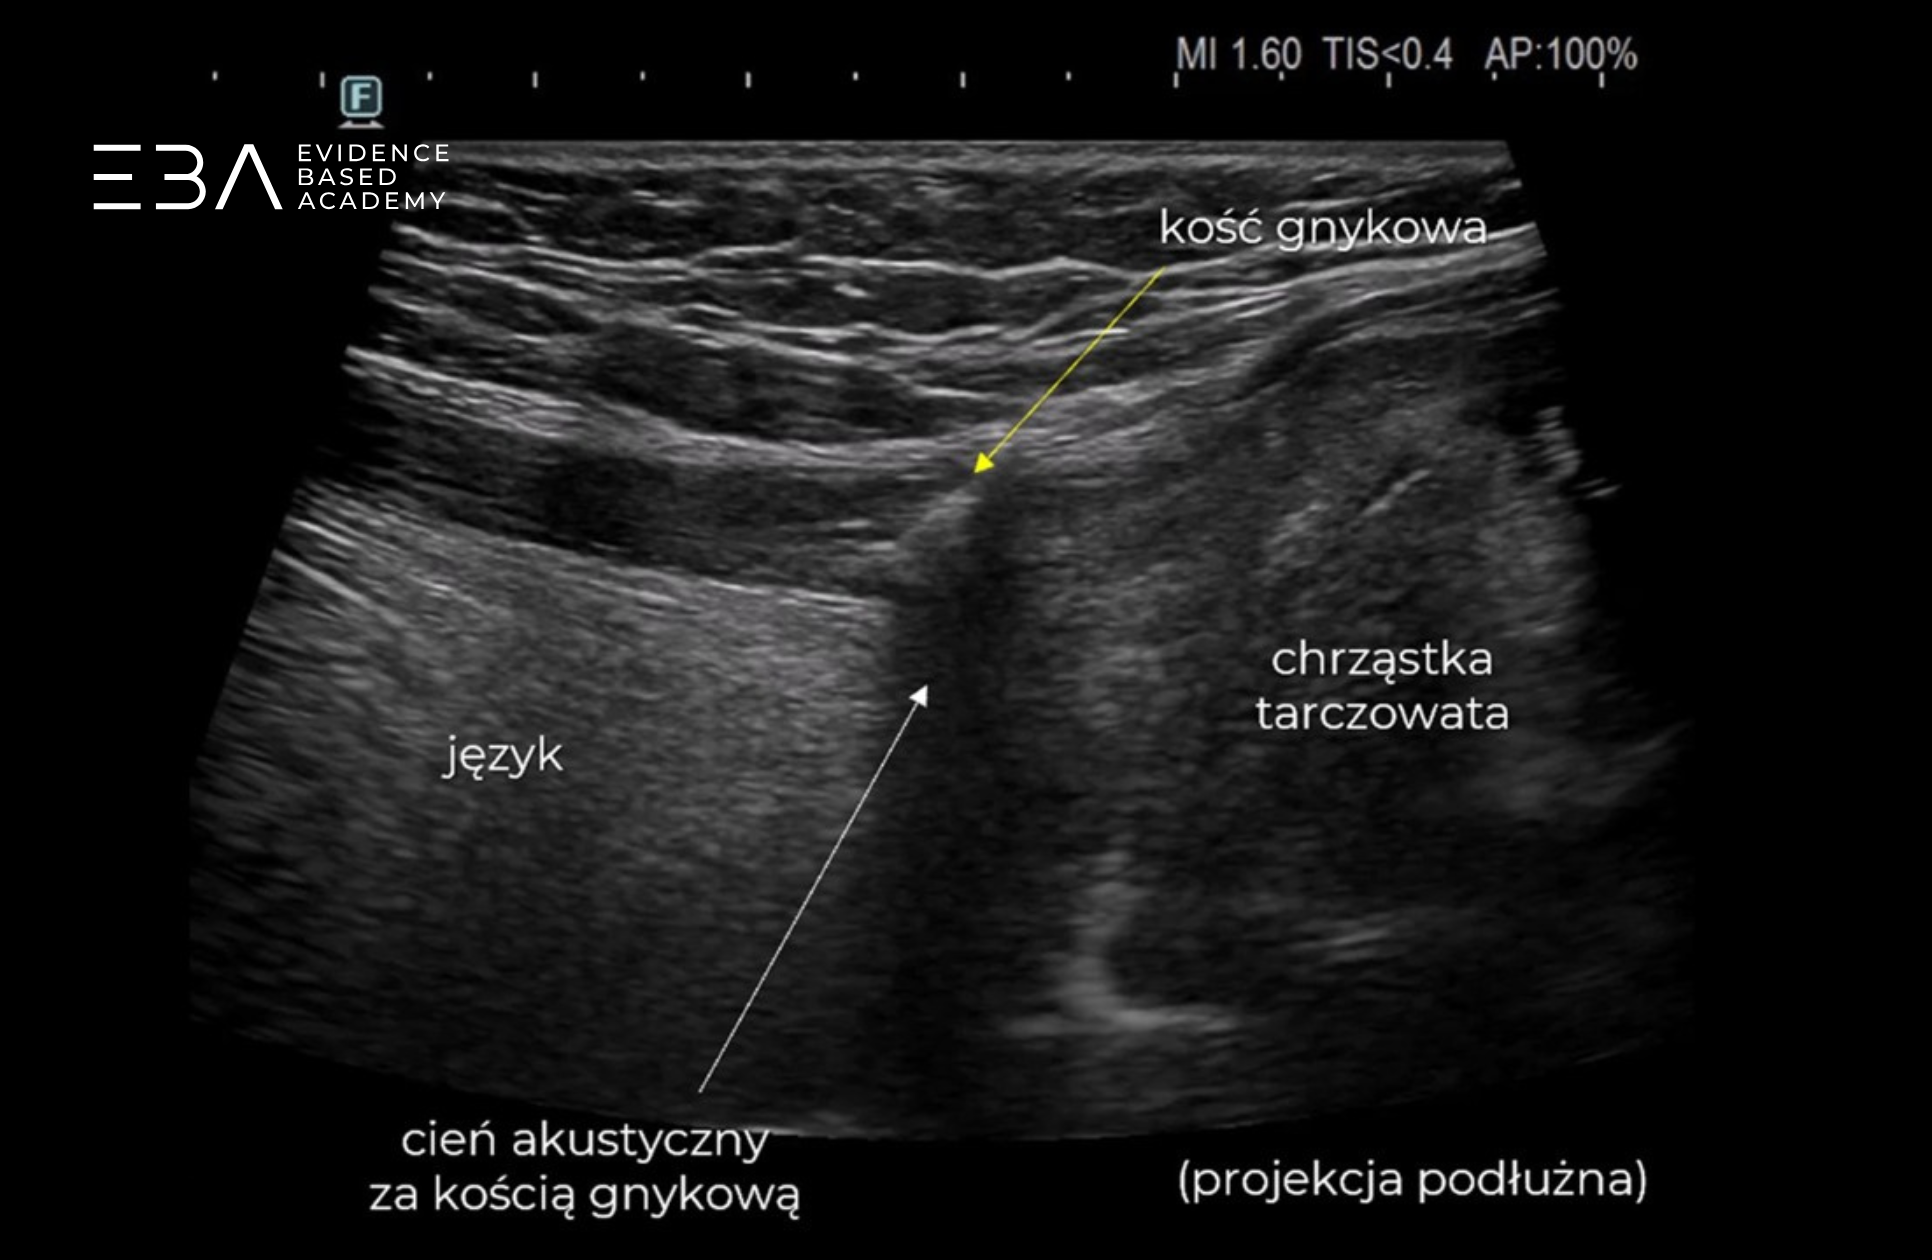

Okolica kości gnykowej – projekcja poprzeczna i podłużna.